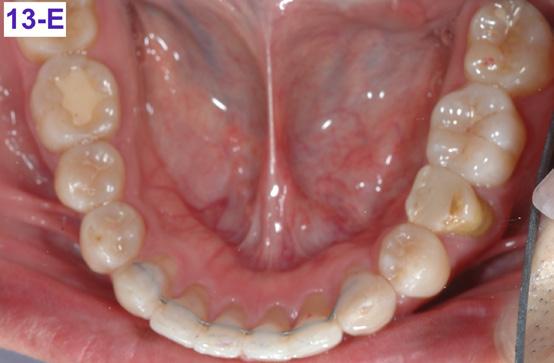

Please view the post-treatment images at the time of insertion of the retainers (Figure 13 – A, B, C. D, E, F, G, H, I, J, K, L).

FIG. 13E: Post-treatment, mandible, occlusal view